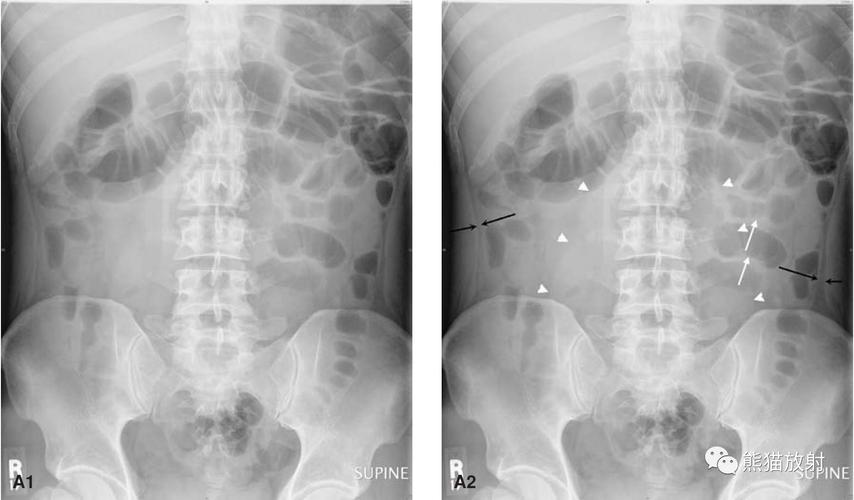

比较典型的腹部平片

腹部站立位平片讨论

腹部平片

腹部平片正常图片

立位腹部平片

腹部平片图

正常腹部平片

腹部气液平面x线图片

肠梗阻腹部平片图片

正常腹部立位平片图片

腹部平片气液平面

正常腹部x线平片图

腹部卧位平片

腹部x线平片

腹部立位片

腹部卧位片

腹部平片气液平面图片